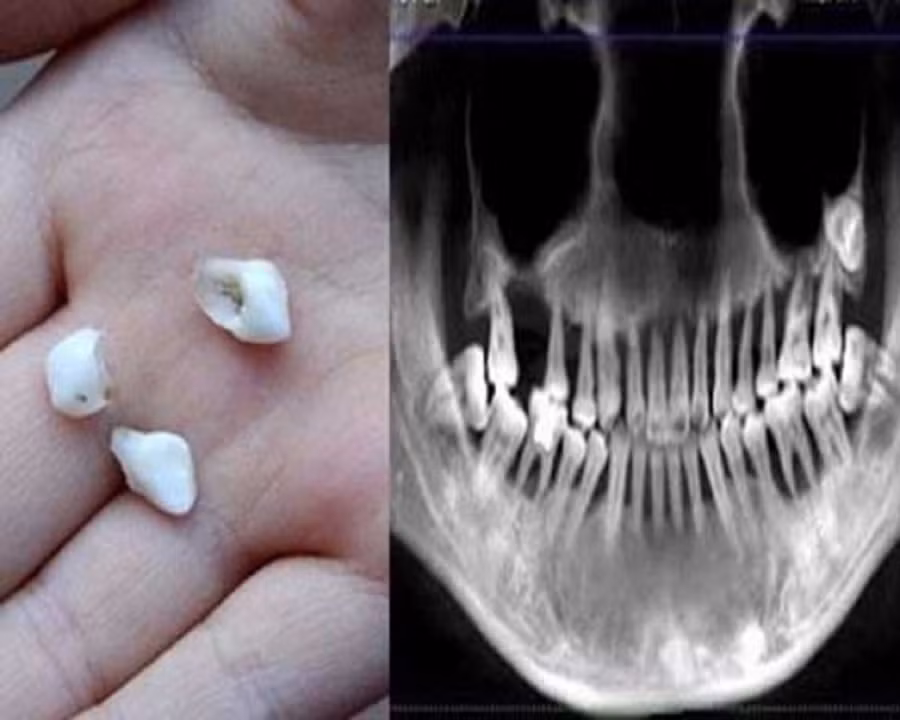

Khi đang chải răng thì răng cửa của Tiểu Manh bất ngờ bị rụng cô vội đến bệnh viện nha khoa Hàng Châu để thăm khám. Tại đây, các bác sĩ kết luận cô bị viêm nha chu nặng và phải nhổ bỏ toàn bộ hàm răng trên. Cô chết lặng sau khi nghe thông báo!

Theo cô cho biết, thời gian trước cô đã bắt đầu thấy răng mình có vấn đề. Các răng thường xuyên ê buốt và yếu dần. Trong suốt 6 năm qua, răng của cô lung lay theo từng ngày, chân răng lộ ra. Cô không thể ăn các món ăn cứng như thịt, trái cây… hầu như chỉ có thể ăn thức ăn mềm, nhão hoặc uống nước canh.

Bác sĩ điều trị cho Tiểu Manh cho biết vì cô đã mắc viêm nha chu từ 6 năm trước, tuy nhiên vì chủ quan không chữa trị một cách triệt để nên bệnh tình ngày một trầm trọng, đến nay các bác sĩ không thể cứu vãn được nữa.

Ngoài ra, Tiểu Manh còn không sử dụng chỉ nha khoa và nước súc miệng cho khiến tình trạng bệnh càng thêm nặng. Hiện tại, răng của Tiểu Manh hầu như không thể tiếp tục sử dụng mà phải nhổ bỏ và trồng răng mới thay thế.